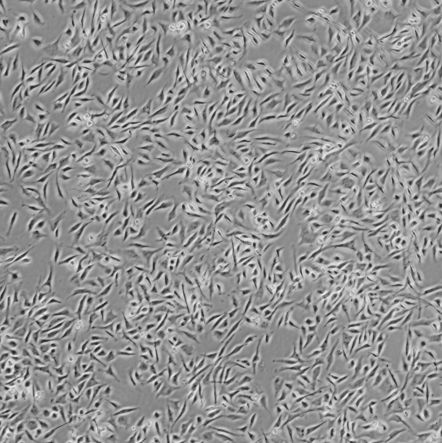

SJRH30_人横纹肌肉瘤细胞

细胞名称: SJRH30_人横纹肌肉瘤细胞

种属来源: 人

种属来源: 肌肉·

生长特性:贴壁生长

细胞形态: 上皮细胞样

培养条件: RPMI1640 +10% fetal bovine serum,37 ℃, 5% CO2

细胞规格: 1 X 106cells/T25或1 mL冻存管

传代方法:1:3传代, 2-3天传1代

冻存条件: 90% FBS + 10% DMSO